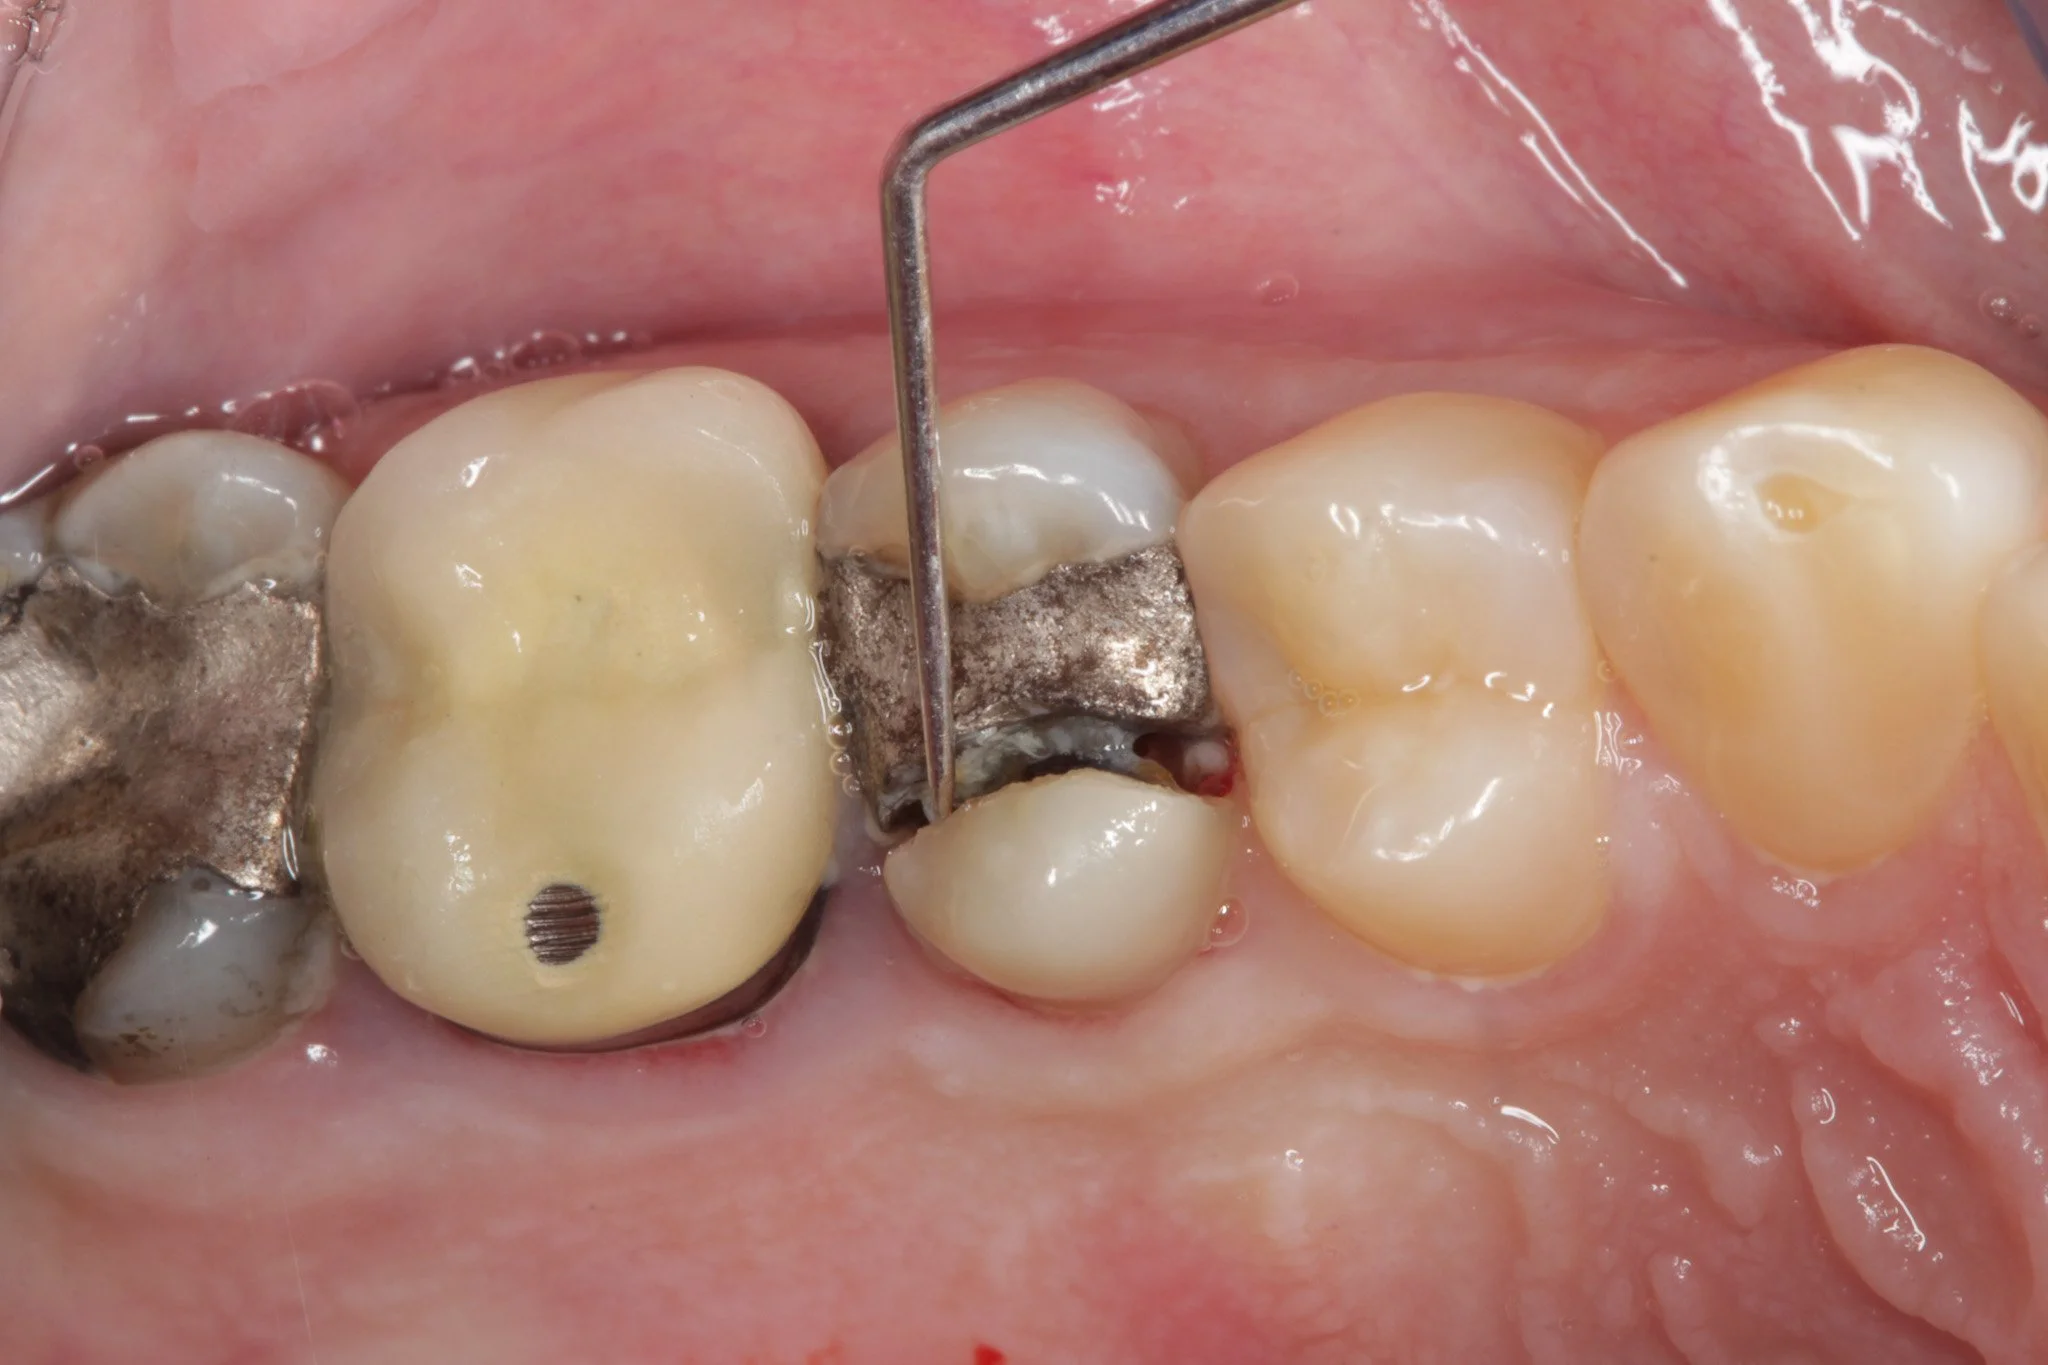

Amalgam Dolgu Nasıl Uygulanır?

Amalgam dolgu uygulaması birkaç aşamadan oluşur ve genellikle tek bir seansta tamamlanır:

- Çürük temizliği: Diş hekimi, çürümüş doku tamamen uzaklaştırılana kadar dişi temizler. Bu aşamada lokal anestezi uygulanır.

- Kavite hazırlığı: Dolgunun tutunacağı boşluk şekillendirilir. Amalgam, mekanik tutuculukla yerinde kalır; yapıştırıcıya ihtiyaç duymaz.

- Amalgam karıştırma ve yerleştirme: Toz metal alloy ile sıvı cıva özel bir cihazda (amalgamatör) karıştırılır. Plastik kıvamdaki karışım hızla dişe yerleştirilir ve sıkıştırılır.

- Şekillendirme ve polisaj: Dolgu, ısırma kuvvetine göre düzeltilir ve pürüzsüzleştirilir. Amalgam birkaç dakika içinde sertleşmeye başlar; tam sertliğe ise 24 saat içinde ulaşır.

Uygulama süreci ortalama 30-45 dakika sürer. İşlem sonrası ilk 24 saat içinde o tarafla çiğnememek, dolgunun sağlam oturması için tavsiye edilir.